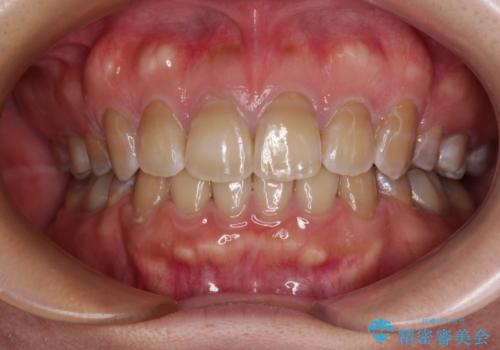

【モニター】処置歯の多い歯列 インビザラインでデコボコを整える